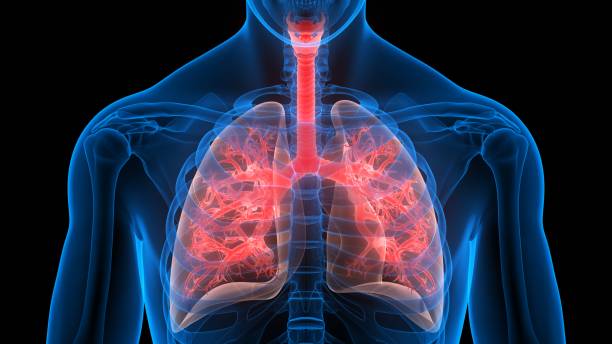

폐섬유화증은 폐조직 내 결손 및 염증에 의해 섬유화 과정이 일어나서, 건강한 폐조직이 염증과 섬유화에 대한 대체물질로 치환되는 질환입니다. 이로 인해, 섬유화된 조직은 신축성이 없고, 호흡기능이 저하됩니다. 따라서 다른 질병과 마찬가지로 초기에 적절한 치료를 받는 것이 중요하기 때문에 이번 시간에는 폐섬유화로 인한 증상들에 대해 정리해보겠습니다.